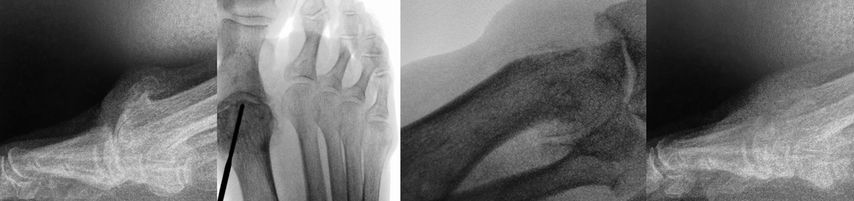

Aufgrund von Problemen mit der Helal- und der Weil-Osteotomie wurden minimalinvasive Techniken entwickelt. Schon 1991 beschrieb Whitedie minimalinvasive distale Metatarsalosteotomie („Distal Metaphyseal Metatarsal Osteotomy“, DMMO).13 Die Endposition des Metatarsalköpfchens wird durch den Zug der intakten Weichteile und die postoperative Vollbelastung diktiert. Vor allem de Prado, Redfern und Vernois haben diese Technik propagiert. Hier wird unter Zuhilfenahme einer minimalinvasiven Fräse mit hohem Drehmoment eine extraartikuläre Osteotomie des Metatarsales von proximal plantar nach distal dorsal durchgeführt. Das plantare Fragment wird unter Druck von distal nach proximal verschoben. Postoperative Zügelverbände gemeinsam mit dem intakten Weichteilmantel sollen die Osteotomie in der gewünschten Stellung stabilisieren (Abb. 4).

Johansen et al.14 präsentierten eine randomisierte Studie mit jeweils 30 Patienten. Die Komplikationsrate war bis auf das vermehrte Auftreten von hypertrophen Narben (0 vs. 9%) in der offenen Weil-Gruppe gleich. Die postoperative Bewegungseinschränkung, die „floating toe“ und eine Plantarflexions- bzw. Hyperextensionsfehlstellung traten bei der offenen Weil-Osteotomie häufiger auf. Die Operationszeit war bei der DMMO-Gruppe signifikant kürzer, dafür war die Röntgenbestrahlungszeit signifikant länger.